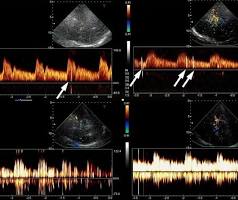

Ako je test izveden pravilno, mikromjehurići  bi trebali proći kroz pluća i biti filtrirane. Ako se pojavljuju na lijevoj strani srca ili mozga (detektovano TCD-om), potvrđuje se postojanje RLS.

Pozitivan test pokazuje da su mjehurići prešli sa desne na lijevu stranu cirkulacije, što sugeriše PFO, ASD ili drugi šant. Težina šanta se često ocjenjuje brojem viđenih mikromjehurića:

• Blagi (Grade 1-2): Pojedini mjehurići na lijevoj strani

• Umjereni (Grade 3): Umjeren broj mjehurića prelazi

• Teški (Grade 4): Velik broj mjehurića brzo prelazi, što ukazuje na veliki ili lako otvoriv šant